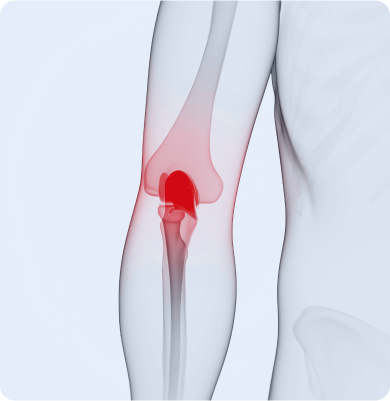

무릎 인대 손상

외부 충격이나 과도한 움직임으로 인해 무릎 관절의 인대가 늘어나거나 찢어지는 질환

주요원인

주로 스포츠 활동 중 갑작스러운 방향 전환, 점프 착지, 외부 충격 등으로 발생합니다. 일상생활 중 무릎을 비트는 동작이나 넘어짐 등도 원인이 될 수 있습니다.

주요증상

• 부기와 압통이 생기고 무릎을 움직이기 어렵습니다.

• 걷거나 체중을 실을 때 무릎에 불안정함을 느낄 수 있습니다.

• 손상 정도에 따라 관절의 움직임 제한 및 관절 불안정성이 동반됩니다.